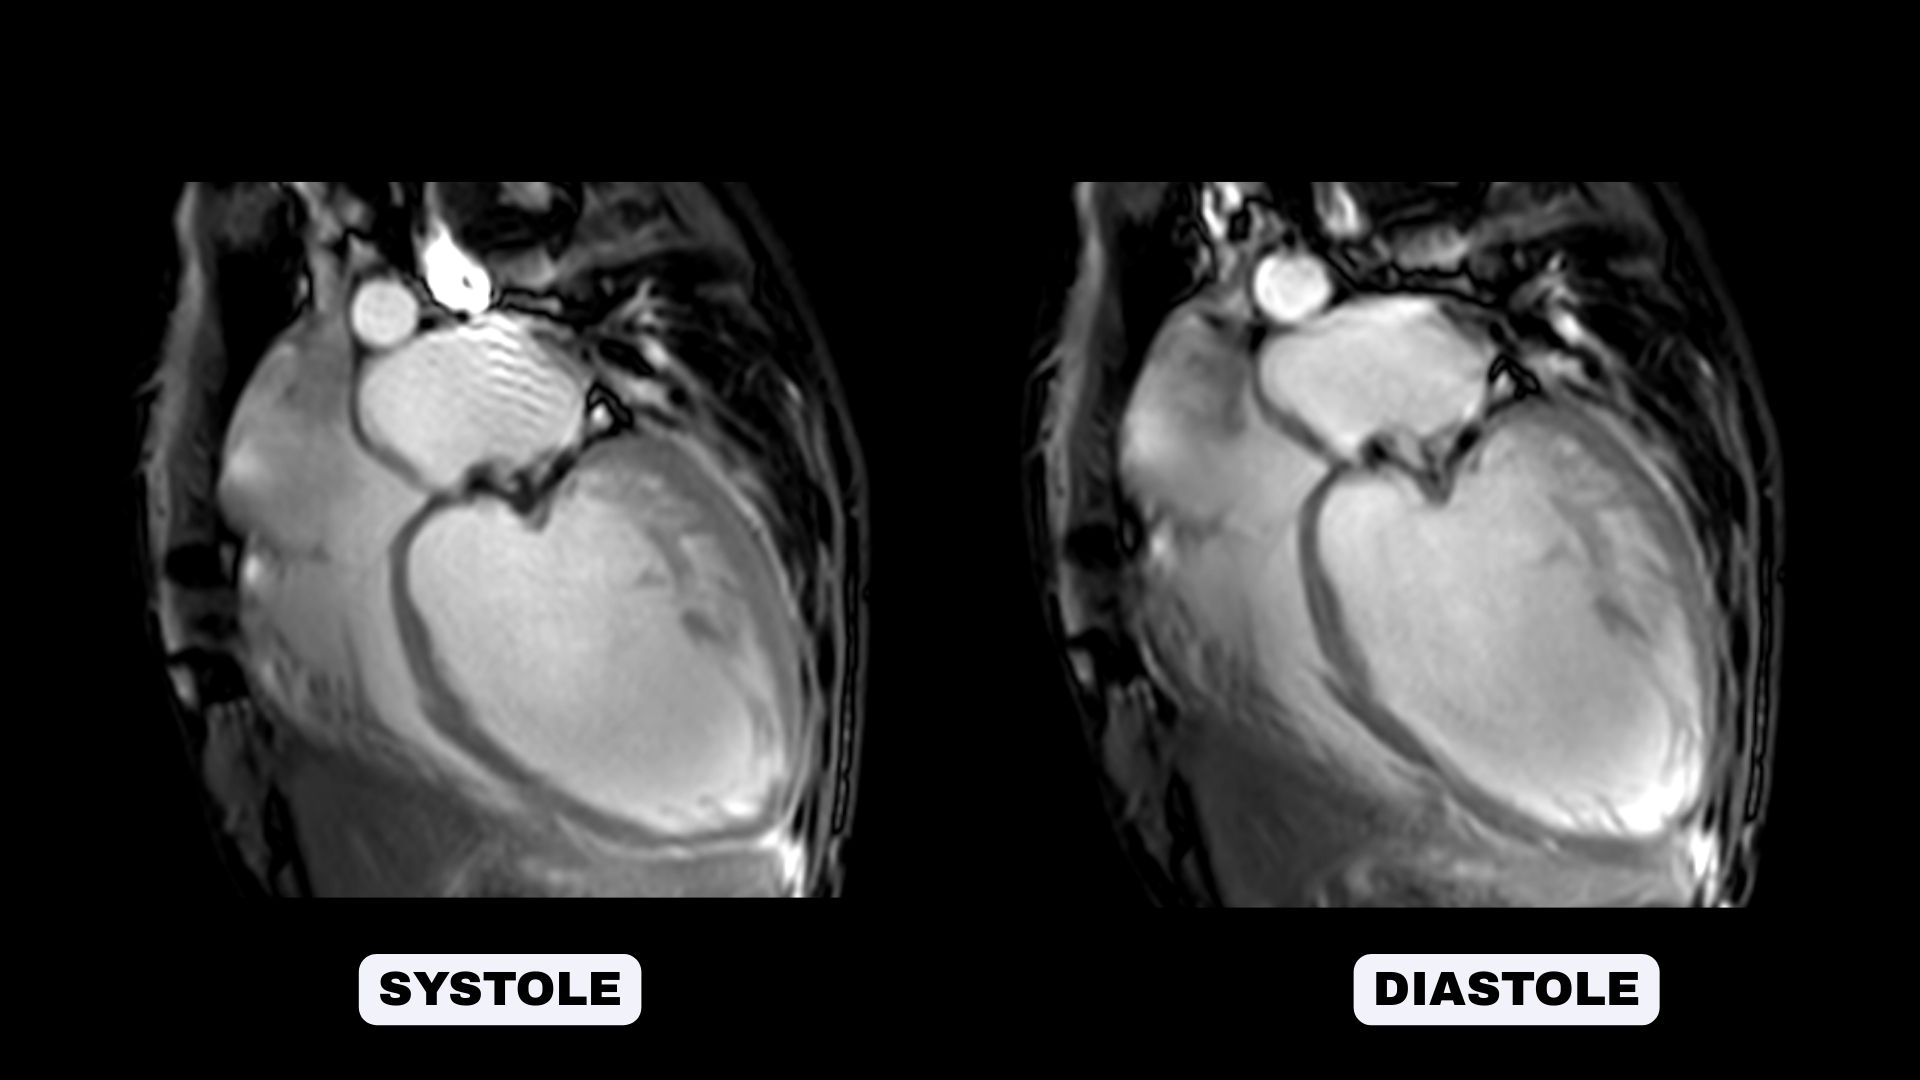

Cine SSFP sequences for morphological and functional evaluation

LGE short-axis images showed a non-ischemic mid-wall pattern in the basal and mid inferoseptal segments.